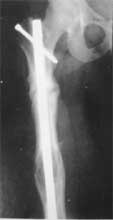

我们已经采用震波治疗了一些长骨、距骨、舟状骨、股骨颈等部位的骨折延迟愈合和骨不连,效果令人鼓舞。

95年9月开始使用超声波         95年10骨痂形成

95年11月继续愈合            96年1月31日完成桥移